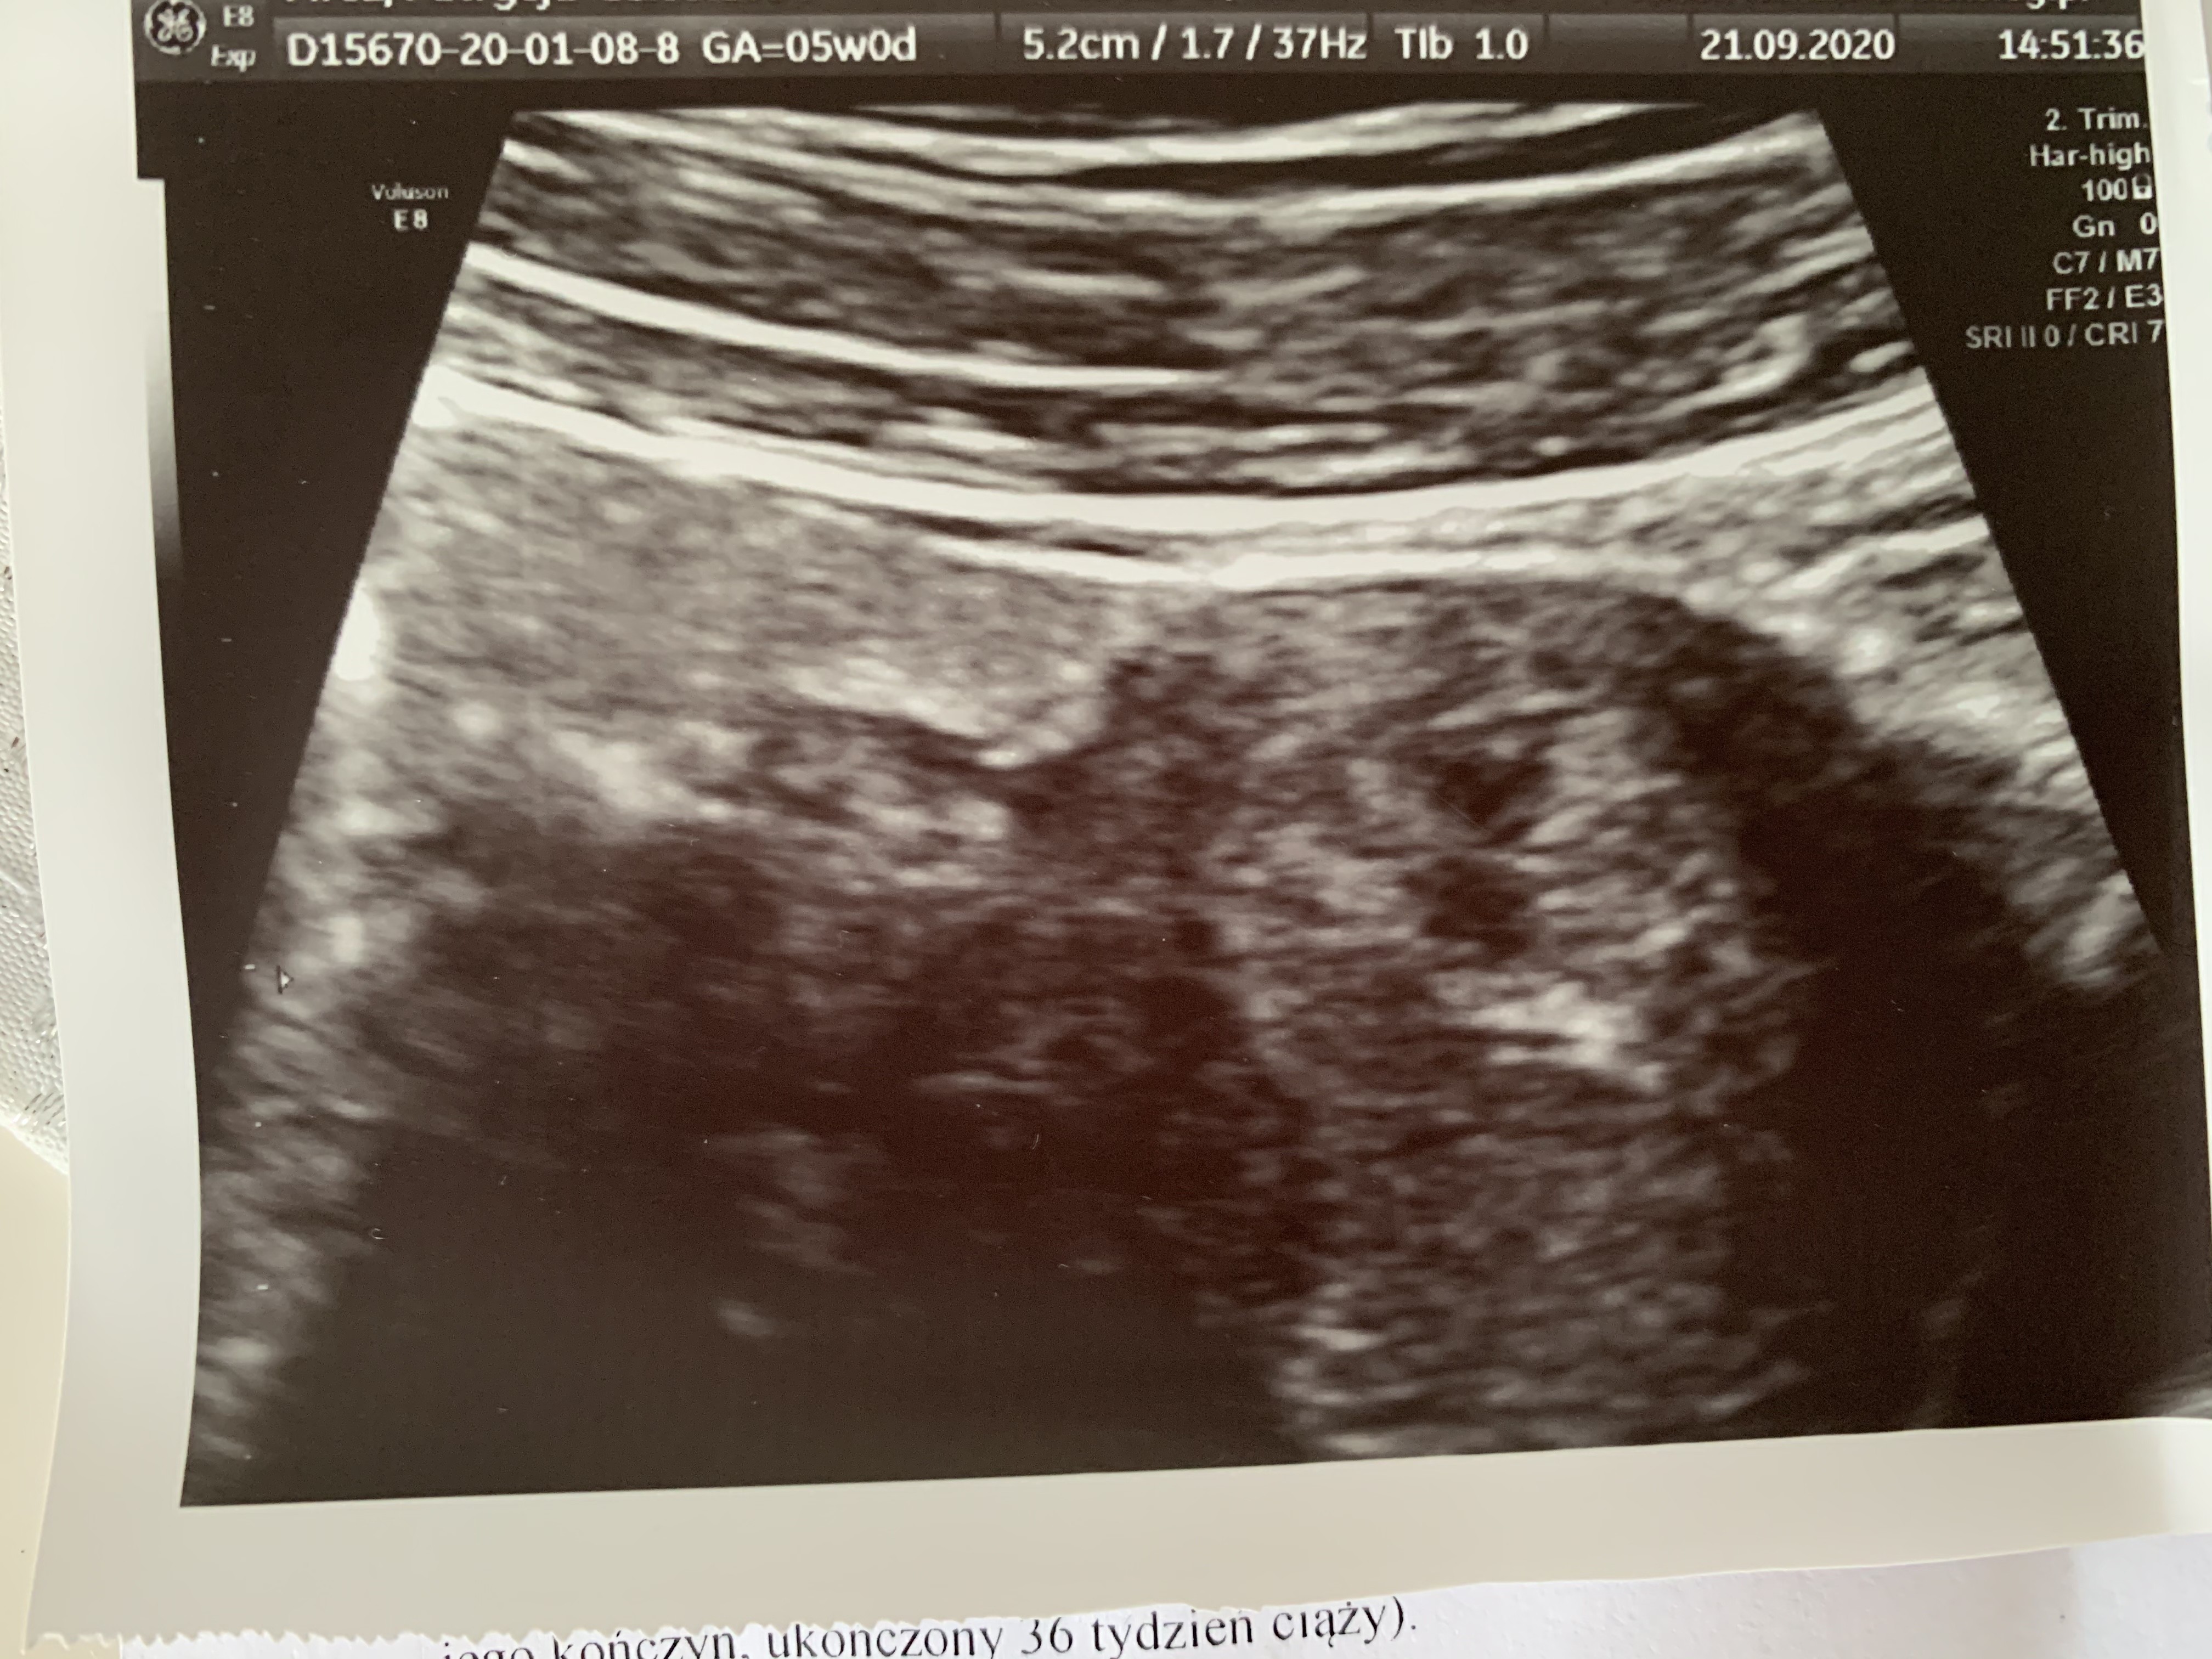

Hej dziewczyny powiedzcie mi bo wariuje to jest 5 tyg. Czy wy tez uważacie ze w tym tygodniu za mało sie rozwijają, nie ma widocznego ys.

Martwię się ze znowu historia się powtarza w opisie mam slabowidoczny pęcherzyk ciążowy.

Kolejna wizytę mam za 2 tyg. 😔